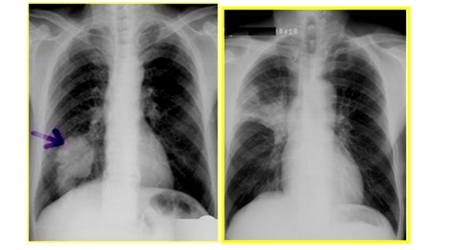

四、肺占位性病变

图中可见肺门不规则肿块,根据部位诊断中央型肺癌

图中可见右下肺分叶状肿块,根据部位诊断周围型肺癌

细支气管肺泡癌

①结节型表现为单个的圆形阴影。

②弥漫型表现为两肺弥漫分布的大小不等的结节

肺部良性与恶性肿瘤的鉴别

| 良性肿瘤 | 恶性肿瘤 | |

| 生长 | 缓慢 | 快 |

| 有无包膜 | 有 | 无 |

| 生长特点 | 对周围组织没有侵犯而表现为圆形、边界清楚光滑的肿块影 | 生长快、异常供血血管多,因血管进入处的阻挡导致肿块生长呈分叶状,因癌性淋巴结炎导致边界短毛刺状改变,肿瘤中心可发生缺血坏死 |